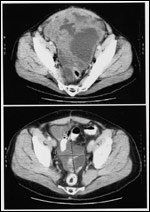

FIGURE 1

Pre- and Posttreatment CT Scans

Based on data from this phase II trial, one GIST patient's response to imatinib is illustrated in Figure 1. This patient had a classic partial and durable response to therapy, as evidenced over a period of 6 months. The initial response data have been substantiated by a recent report with longer follow-up.[29]